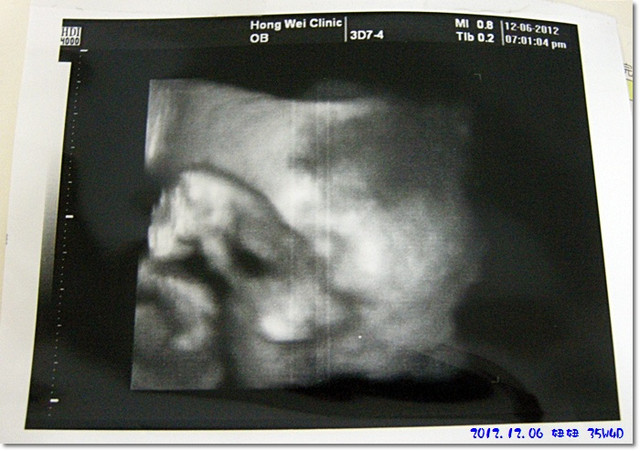

下面這張就是妞妞的3D圖像...

妞妞的手一直擋在她的臉面前,都不露出真面貌內![]()

把圖片轉個方向看應該會比較清楚一點也比較可以意會吧...

我個人是看不太出來啦

,虧陶醫師一直在跟我解釋圖像的樣子

我還是有看沒有懂呀![]()